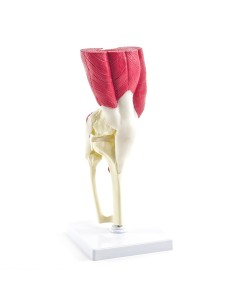

Ginocchio,W47007 modello di lusso